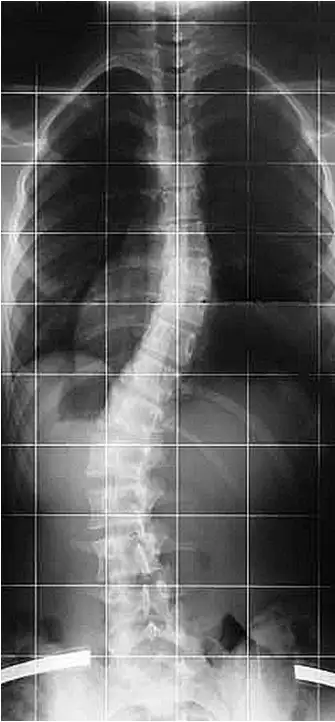

Điều trị vẹo cột sống

Có nhiều nguyên nhân khác nhau dẫn đến vẹo cột sống, bao gồm di chứng của bại liệt, bại não, tật nứt đốt sống, dị tật đốt sống và chấn thương hệ thần kinh-cơ-xương, nhưng trong phần lớn các trường hợp, không xác định được nguyên nhân cụ thể. Trường hợp này được gọi là vẹo cột sống vô căn (nghĩa là không rõ nguyên nhân).

Vẹo cột sống vô căn (Idiopatic Scoliosis): là tình trạng cột sống bị cong, vẹo mà không rõ nguyên nhân Đây là dạng thường gặp nhất trong các loại vẹo cột sống có cấu trúc cố định (tức là cột sống cong thật, không phải do tư thế). Bệnh thường bắt đầu ở trẻ em hoặc thanh thiếu niên và có thể nặng dần lên cho đến khi cơ thể ngừng phát triển xương (khoảng sau tuổi dậy thì). (Stagnara, 1988.)

Việc đeo Áo chỉnh hình (orthosis) thường có thể điều trị vẹo cột sống, tuy nhiên nếu góc cong của cột sống vượt quá 45º thì sẽ rất khó điều trị bằng phương pháp này. (Thomas M. Gavin và cộng sự, 2001)

Điều trị bằng nẹp chỉnh hình được khuyến nghị cho những bệnh nhân chưa trưởng thành về mặt xương khớp và có độ cong tiến triển từ 25º đến 45º (theo góc Cobb), trong khi phẫu thuật cố định cột sống được chỉ định cho các trường hợp có độ cong vượt quá 45º. (Thomas M. Gavin và cộng sự, 2001)